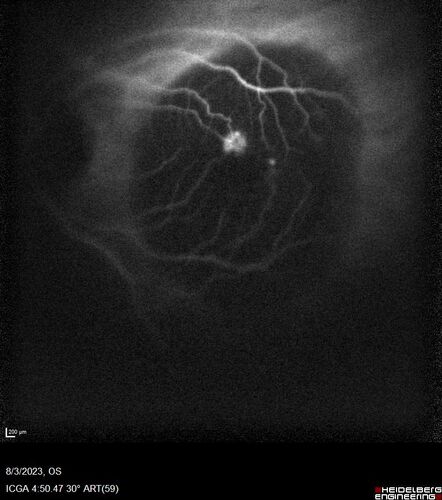

Wet AMD - Type 1 CNVM - RAP lesion

92 year old man with vision loss and very high PED. Because of worry about a PED tear, patient was treated with avastin, then lucentis, then eyelea, then vabysmo (progressively stronger meds)